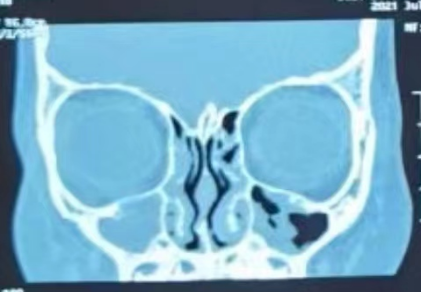

儿童鼻窦炎,不是一个孤立的疾病,常紧随”感冒”,“伤风”,如果感冒1周后脓性鼻涕不少反多,就应该考虑鼻窦炎(如下图)。